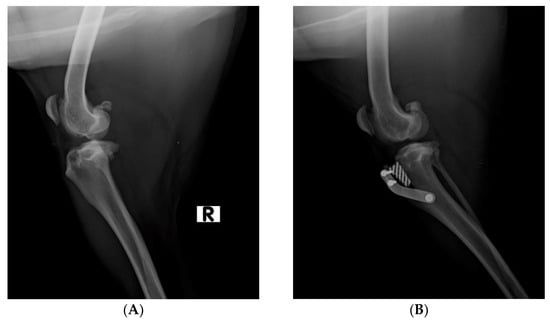

2.2. Surgical Procedure